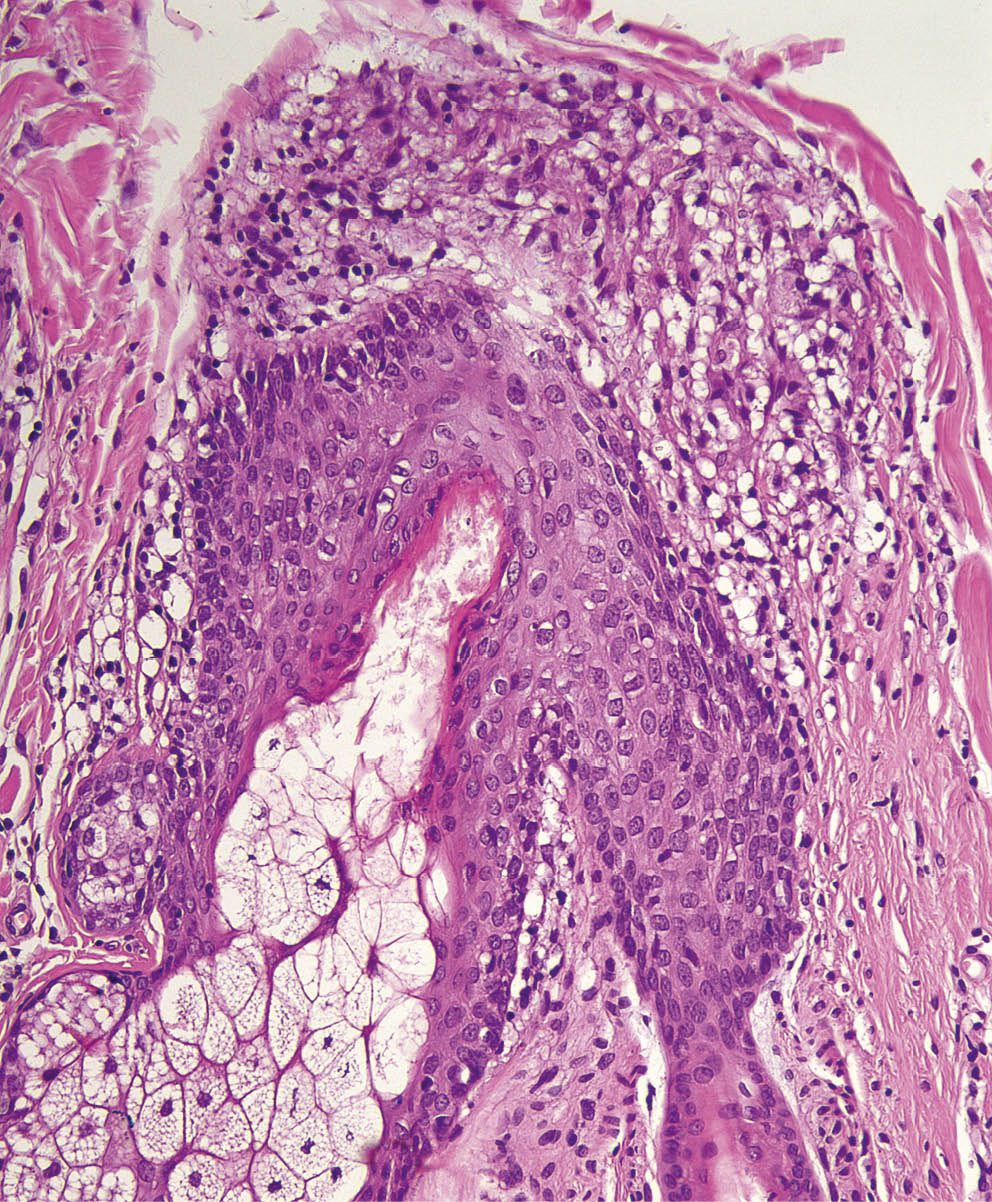

При гистологическом исследовании высыпаний при саркоидозе обычно обнаруживаются эпителиоидноклеточные гранулемы в дерме или подкожной жировой клетчатке, содержащие эпителиоидные клетки, гистиоциты и гигантские клетки, по периферии гранулем могут располагаться лимфоциты в небольшом количестве; в 20% случаев в центре гранулемы отмечается фибриноидный некроз [16]. У нашей пациентки при гистологическом исследовании определялись саркоидные гранулемы, расположенные в дерме вокруг инфундибулярной части волосяных фолликулов, состоящие из эпителиоидных и гигантских клеток (рис. 2–4).

Рис. 2. Волосяной фолликул практически на всем протяжении окружен сливающимися гранулемами саркоидного типа

Рис. 3. Саркоидные гранулемы состоят преимущественно из эпителиоидных клеток

Рис. 4. Саркоидная гранулема прилежит к фолликулярному эпителию у места впадения протока сальной железы в фолликул